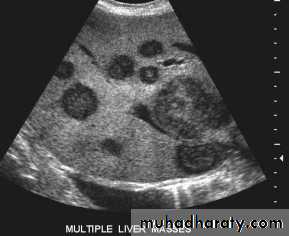

Focal masses ultrasound

Multiple masses